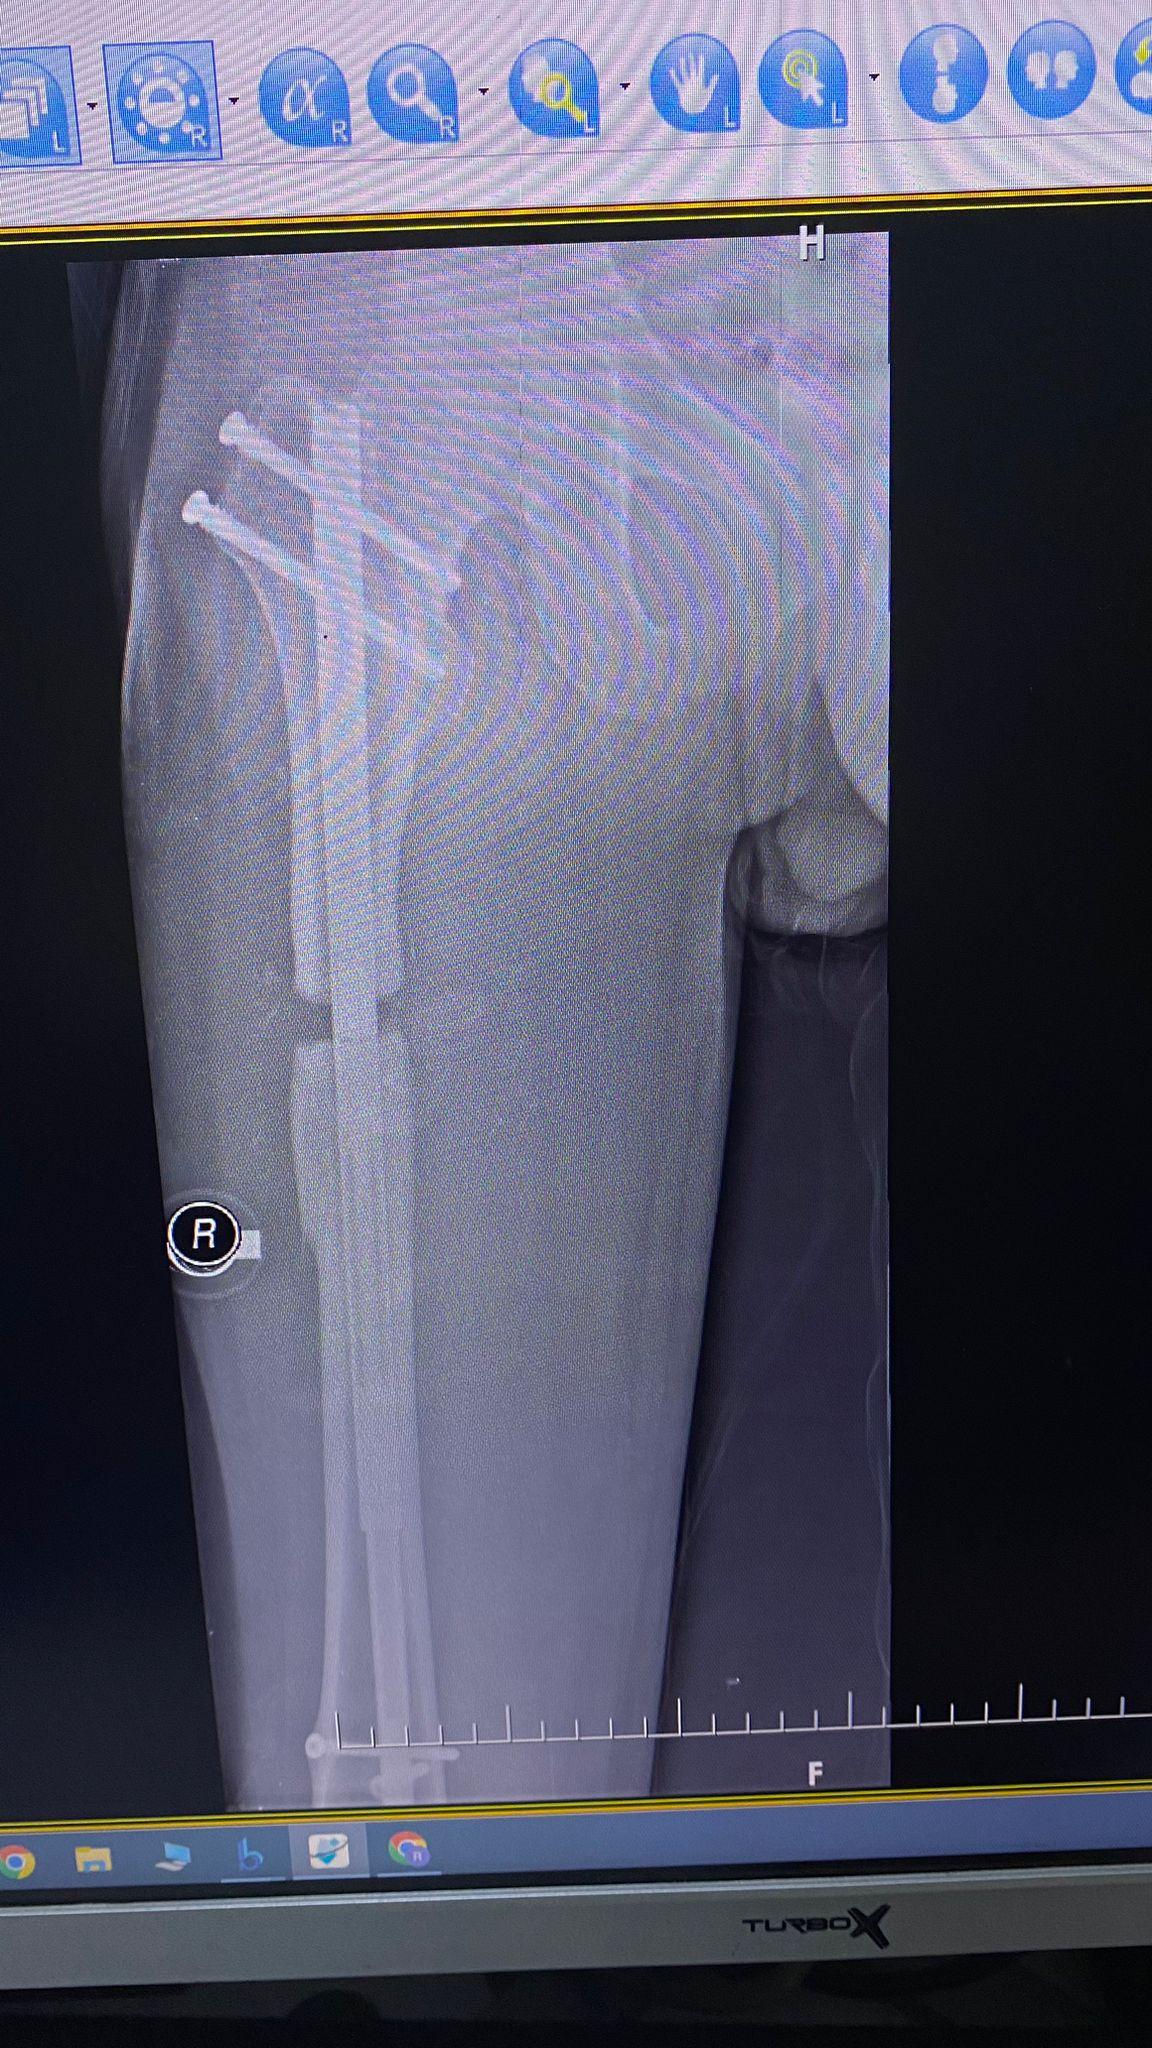

Precice 2 uzuv uzatma sistemi, ABD merkezli tıbbi cihaz üreticisi NuVasive tarafından geliştirilmiş yüksek teknoloji bir içten uzatma yöntemidir. Bu sistem, kemiğin içine yerleştirilen biyouyumlu bir çivi ve dışarıdan kullanılan ERC (External Remote Controller) sayesinde kemiğin kontrollü ve hassas bir şekilde uzatılmasını sağlar.

Precice 2, kemiğin içine yerleştirilen titanyum bir çivinin manyetik güçle kontrollü şekilde uzatılması prensibiyle çalışır. Hastalar, günde üç kez ERC cihazı ile her seferinde 0,33 mm olmak üzere kemik uzatması gerçekleştirir.

Tibia ve Femurda Yüksek Uzama Kapasitesi

• Tibia: 6 cm

• Femur: 8 cm’ye kadar güvenli uzama sağlar.